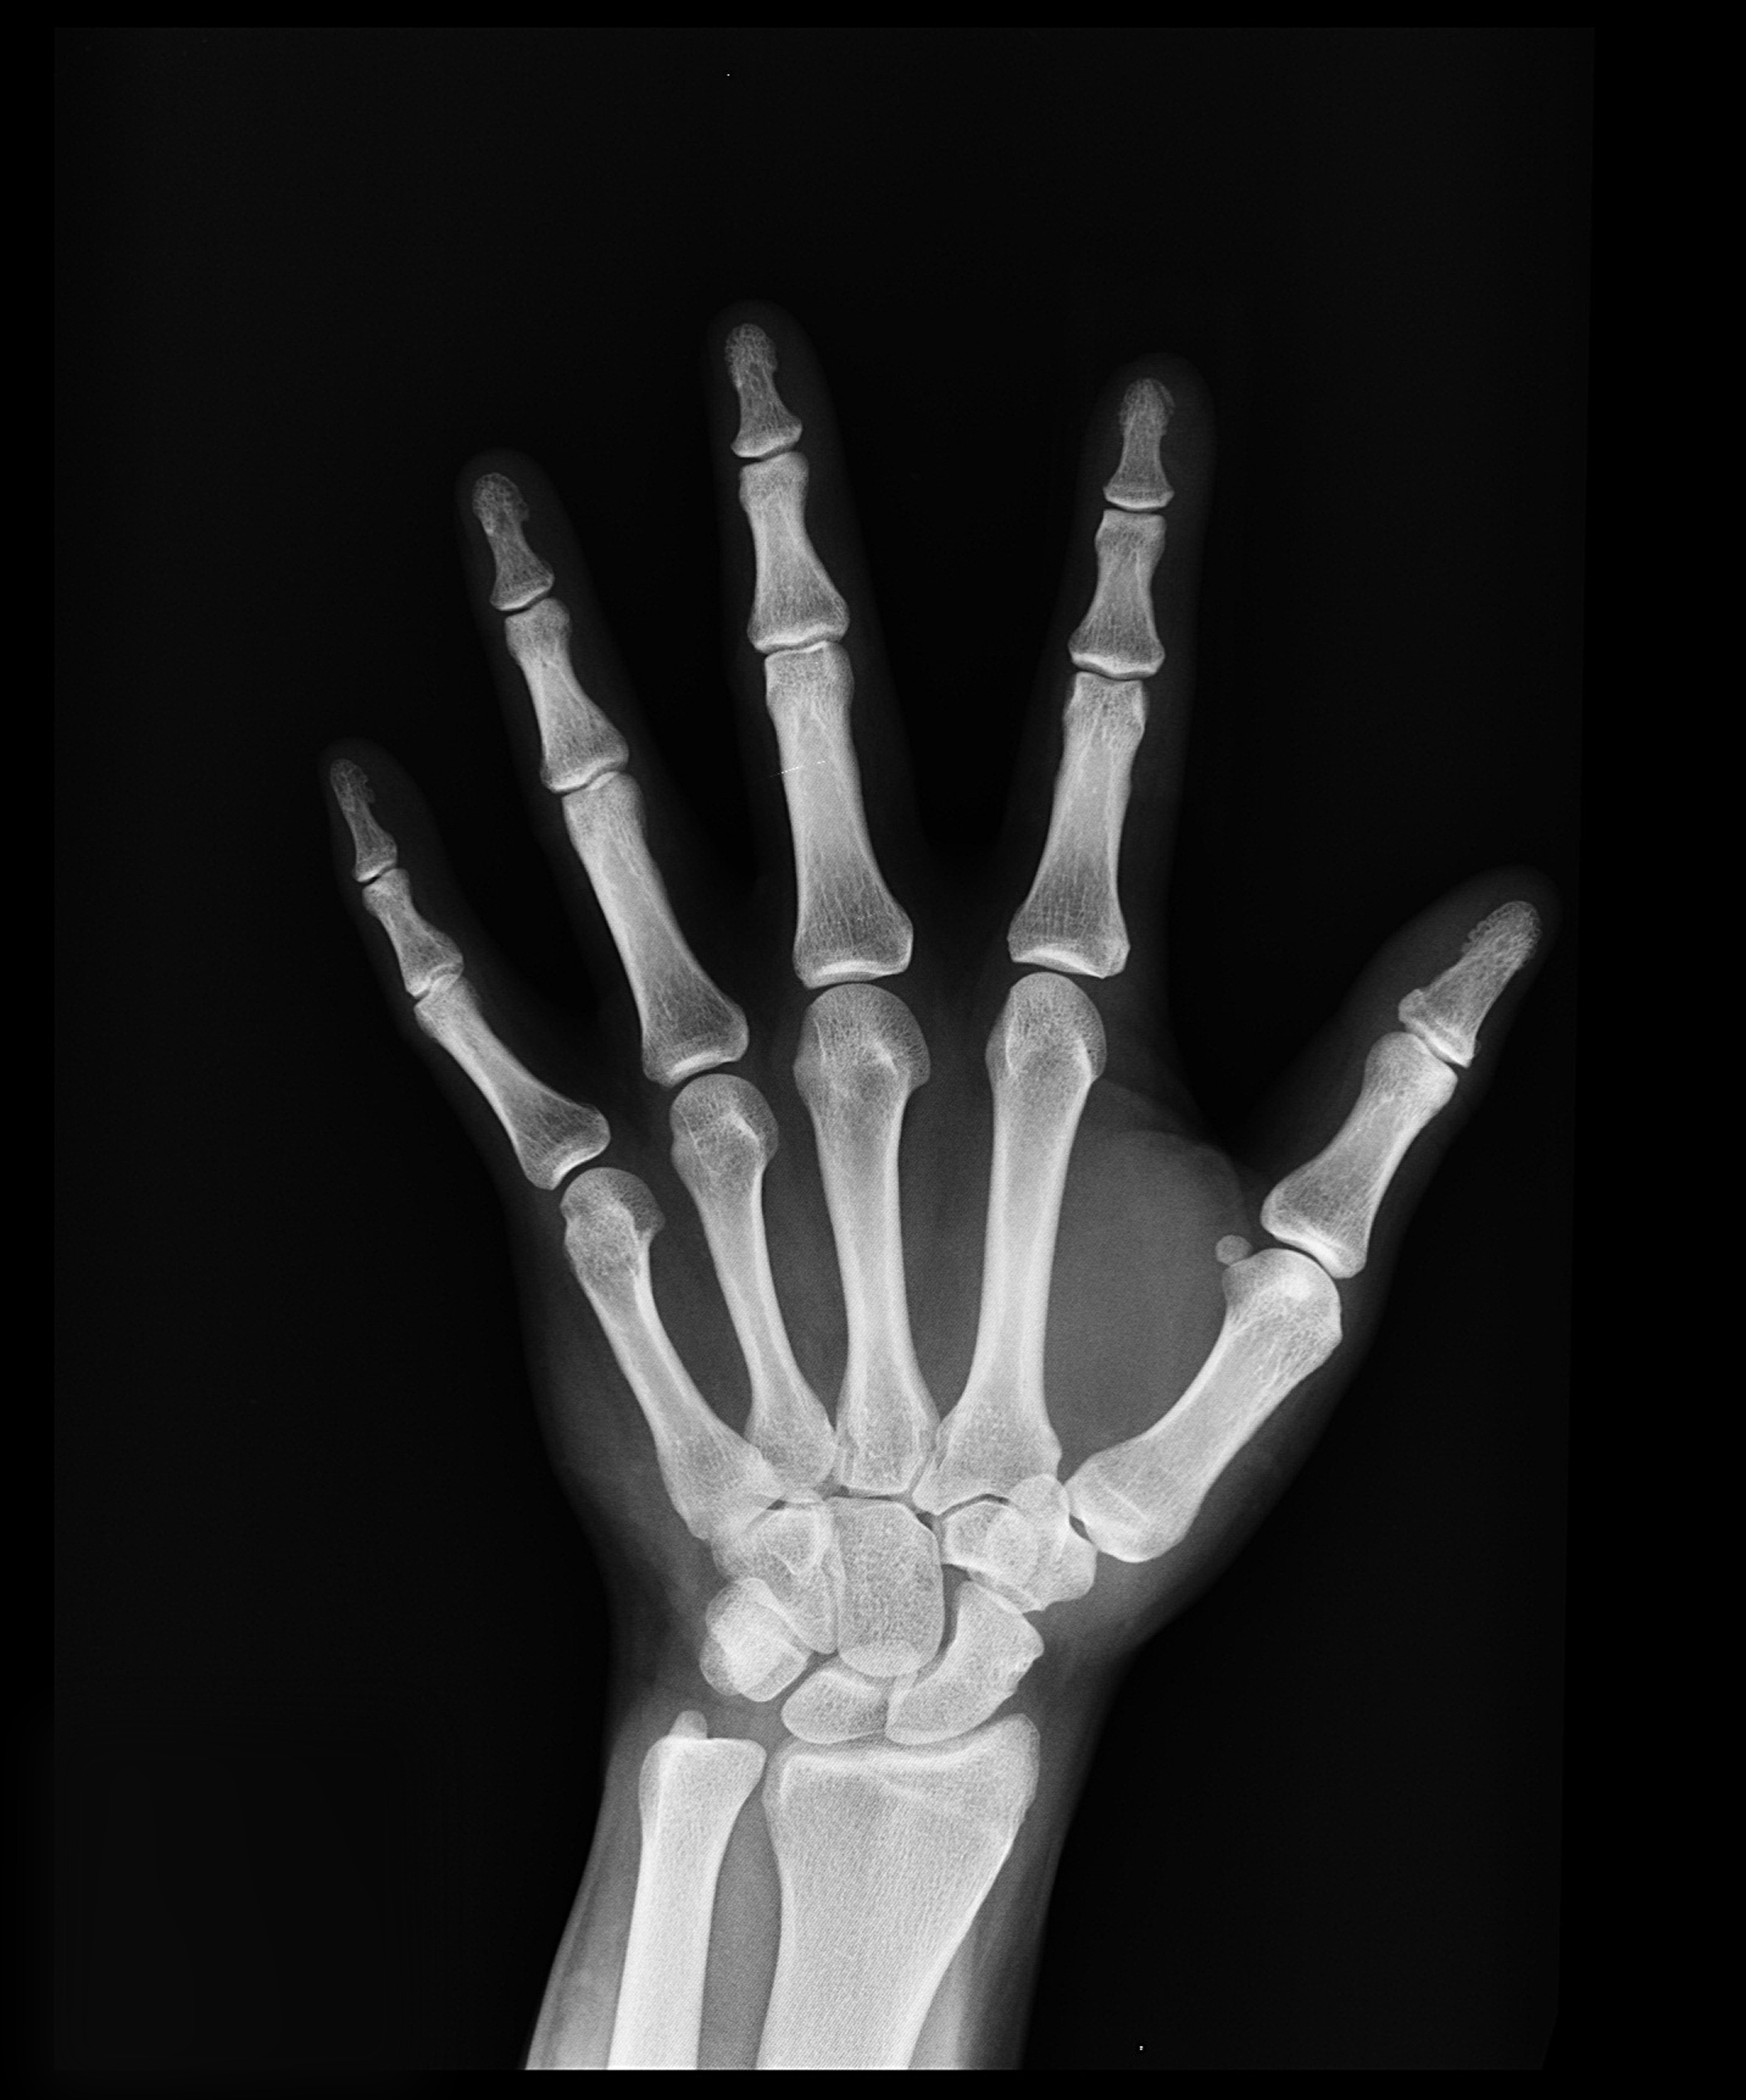

1)관절 건강

MSM은 관절 건강에 유익한 영향을 미치는 것으로 알려져 있습니다.

MSM은 염증을 줄이고 관절의 운동성을 향상시켜 운동 선수들과 관절염이 있는 사람들에게 도움이 될 수 있습니다.